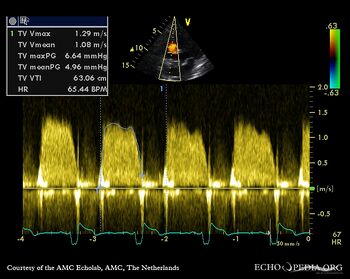

Tricuspid valve stenosis

Courtesy of: AMC Echolab, AMC, The Netherlands

A4CH: doming of tricuspid valve leflets, pacemaker lead in situ Continuous-wave Doppler signal of transtricuspid flow